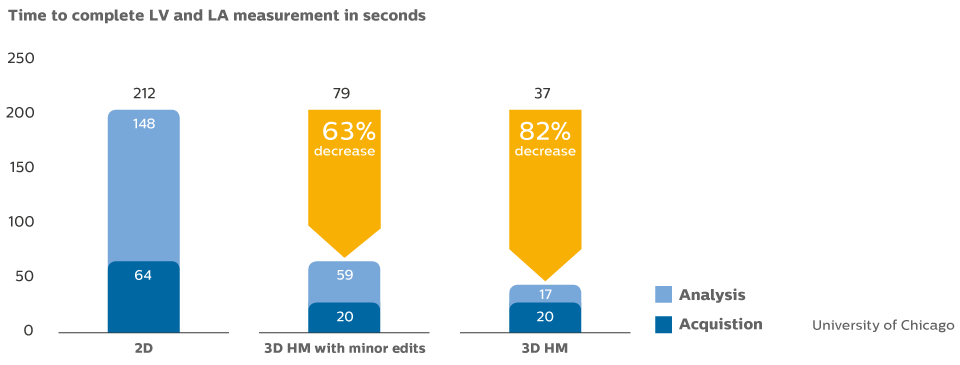

HeartModelᴬ⋅ᴵ⋅ for echocardiography

This study compared quantification between 2D and Live 3D HeartModelᴬ⋅ᴵ⋅ and demonstrated a 82% time savings for HeartModelᴬ⋅ᴵ⋅ when using the automated capability, and 63% time savings when minor edits were required.